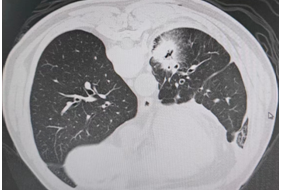

术前

患者(男性,60岁)因长期咳嗽、胸痛等症状入院,经CT检查、支气管镜及肺穿刺活检,确诊为肺腺癌。

在廖江荣的指导下,榕江县人民医院医生通过CT精准定位肿瘤位置,为患者实施CT引导下经皮肺穿刺微波消融术,使用微波消融针将微波能量直接作用于肿瘤组织,使肿瘤细胞凝固性坏死,整个手术仅短短30分钟便顺利完成。术后,患者未出现任何不良反应,恢复良好。